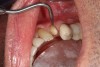

A 71-year-old man presented with acute pain in tooth No. 29 that was spontaneous, unresponsive to vitality testing, and sensitive to percussion. He was referred to an endodontist for treatment of acute apical periodontitis due to the non-vitality of the nerve. Because of the multiple restorations and lingual decay of the tooth, enamel and dentin were compromised, causing the tooth to be biomechanically at high risk and requiring an eventual post-and-core and crown (Figure 1 and Figure 2). Endodontic care included nonsurgical intracanal therapy and creating room for a post space.

Fig 2. Preoperative view of tooth to be restored shows defective Class 5 restoration that unfortunately was mirrored on the lingual gingival margin.

Figure 2